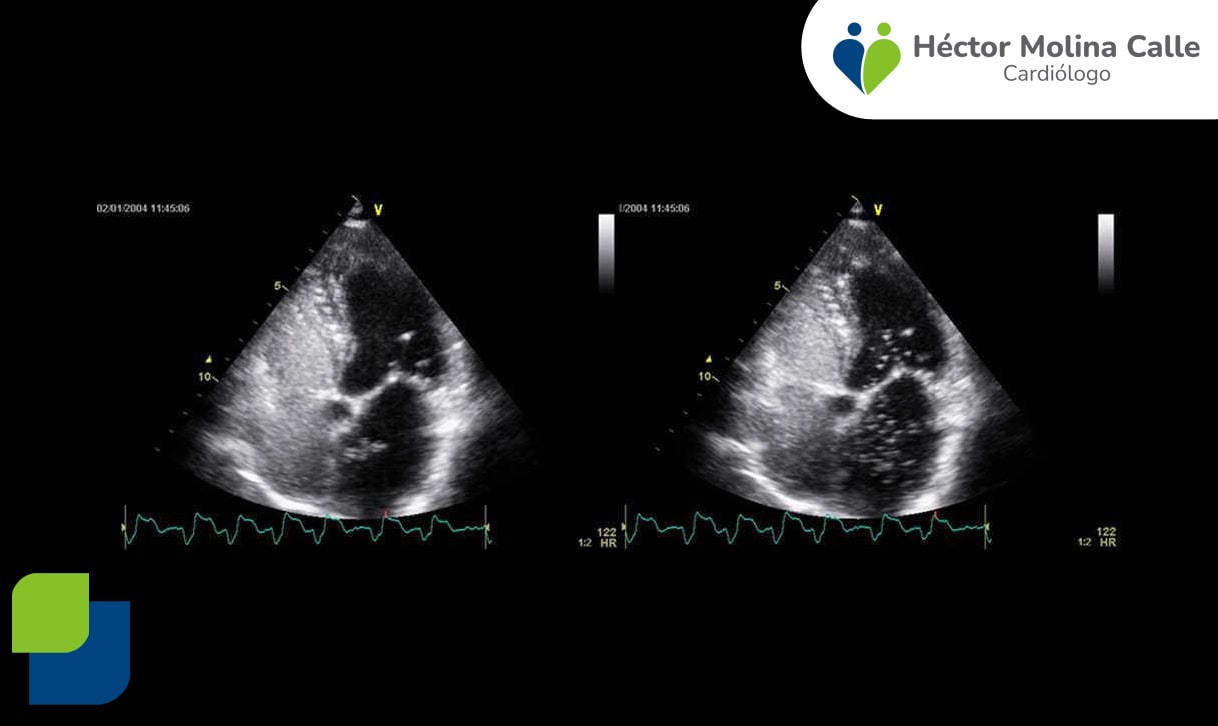

Ecocardiograma de estrés

El ecocardiograma de estrés estudia el comportamiento del corazón ante una situación de aumento de esfuerzo, ya sea a través del ejercicio o de un fármaco, lo que permite observar si el corazón recibe el suficiente flujo de sangre a través de sus arterias coronarias y el correcto funcionamiento de las válvulas cardíacas.

Se realiza combinando el uso del ecocardiograma transtorácio con el ecocardiograma de ejercicio, o bien se administra un fármaco (dobutamina) que actúa como simulador de ejercicio en reposo (ecocardiograma de estrés farmacológico).